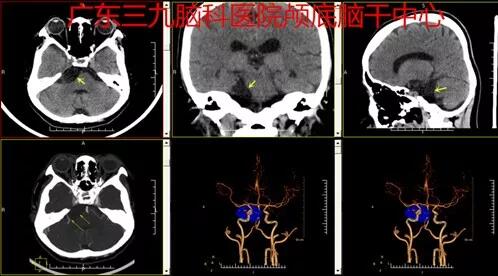

图1:术前头颅CTA检查示右侧桥小脑角区低密度占位性病变内未见异常血管,后缘紧贴一小血管,内缘紧贴基底动脉。